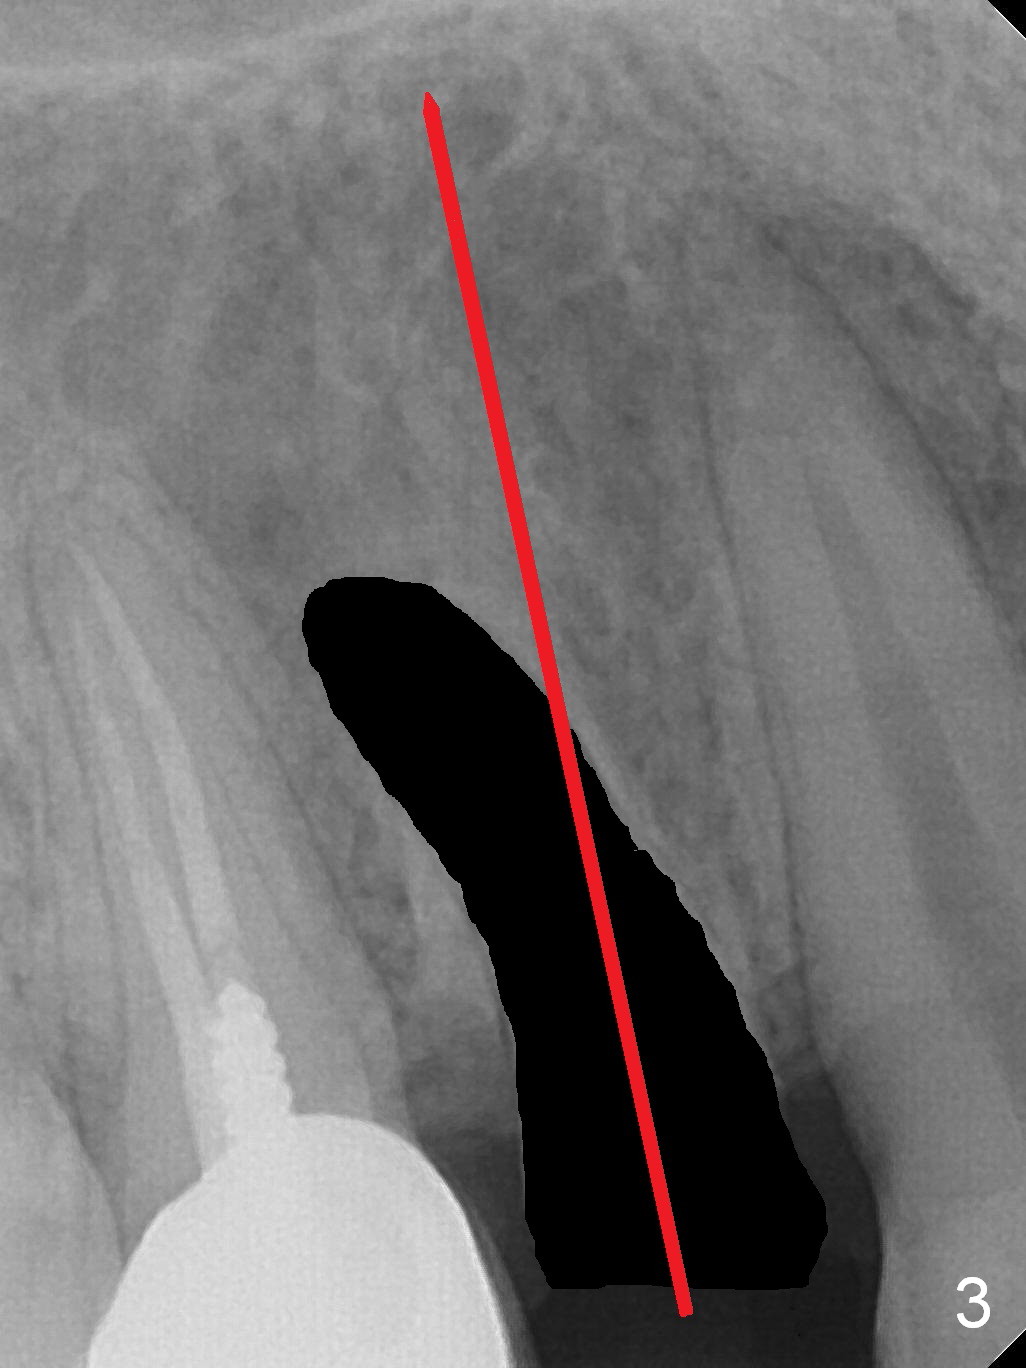

A 34-year-old man (smoker, half a pack a day) has residual root at #5 (Fig.1) with large periapical radiolucency (Fig.2 red dashed line). Since the root curves distally (Fig.3 black area, Clindamycin), osteotomy will be established in the mesial wall (red long arrow). A 3.8x16 or 18 mm implant is to be placed for primary stability (Fig.4). To reduce periimplantitis associated with smoking, place the implant deep. The implant appears to have better surface treatment. Pack sufficient bone graft and membrane. Immediate provisional should have good seal. To place the implant deep, osteotomy will be attempted with a long 1.5 mm pilot drill (PA), followed by 2 mm one with extension and 3.0x18 mm drill.